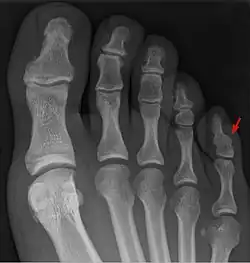

![]() Una radiografia de un pie con sinfalangismo pedal (afectando al dedo meñique del pie), el tipo de sinfalangismo más común | ||

El tipo de sinfalangismo más común es aquél que afecta al dedo meñique del pie, también conocido como sinfalangismo pedal, al igual que el pie de Morton, el sinfalangismo pedal es considerado una variante normal asintomática del pie, afectando aproximadamente al 35-80% de la población.[7]